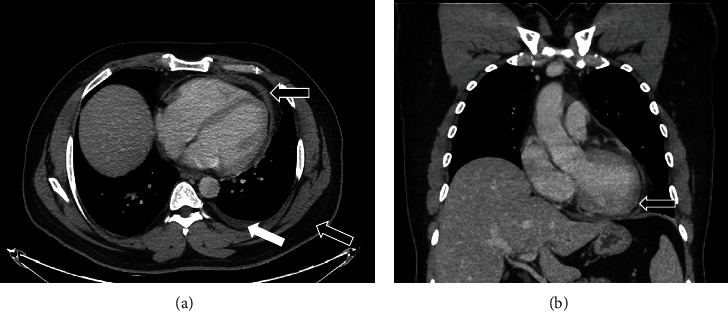

背景:新冠肺炎疫苗临床试验报告了mRNA疫苗(阿斯利康)帮助控制疾病的安全性和有效性。以前很少有报告显示与COVID-19疫苗相关的各种副作用,其严重程度各不相同。在接受我们报告的mRNA COVID-19疫苗的人群中观察到心包炎和心肌炎的可能性。急性炎症性心包炎在首次接种该疫苗后可能是一种罕见的症状,在COVID-19时代分享这种罕见的症状对于更好地管理和接种疫苗后的结果是有益的。案例演示。这是一例健康成人患者在接受阿斯利康COVID-19疫苗第一剂后出现急性炎症性心包炎伴少量心包积液的病例,除COVID-19 PCR阴性外,无其他提示其他病毒性疾病的症状。一名48岁的健康男性在接种第一剂新冠肺炎阿斯利康疫苗9天后出现。该症状始于接种疫苗后3天,当时他主诉进行性胸痛,伴有低烧和全身乏力,几天后出现用力性呼吸困难。诊断为急性炎症性心包炎伴少量心包积液,并给予相应治疗。一星期后,病人的临床表现明显改善,心包积液得以消除。39天后,急性心包炎的影像学表现明显好转。结论:目前正在进行的COVID-19疫情仍在调查中,尽管多种疫苗已被证明对COVID-19有效,但由于我们不断了解这种新型疾病,指南仍在定期修改。然而,我们报告了一例在首次接种阿斯利康COVID-19疫苗后出现独特临床表现的病例,在文献中尚未广泛报道,这可能有助于提高人们对COVID-19疫苗接种后可能诊断和炎症性心包炎可能性的认识。

Background: Clinical trials of the COVID-19 vaccine reported the safety and efficacy of mRNA vaccines (AstraZeneca) to help control the disease. Few previous reports have shown various side effects associated with COVID-19 vaccines that vary in severity. The possibility of pericarditis and myocarditis has been observed in people who have received an mRNA COVID-19 vaccine which we are reporting. Acute inflammatory pericarditis can be a rare presentation after receiving the first dose of this vaccine, and it is enriching to share such rare presentations in the era of COVID-19 for better management and outcomes after vaccination. Case Presentation. This is a case of acute inflammatory pericarditis with a small pericardial effusion after receiving the first dose of AstraZeneca COVID-19 vaccine in a healthy adult patient who had no other symptoms suggestive of other viral illness in addition to the negative COVID-19 PCR. A 48-year-old healthy male presented nine days after receiving the first dose of COVID-19 AstraZeneca vaccine. The symptoms started three days after the vaccine, when he complained of progressive retrosternal chest pain with low-grade fever and generalized fatigue, followed by exertional dyspnea after a few days. The diagnosis of acute inflammatory pericarditis with small pericardial effusion was established, and the patient was accordingly treated. One week later, the patient showed significant clinical improvement with the resolution of his pericardial effusion. After 39 days, there was a significant radiological resolution of signs of acute pericarditis.